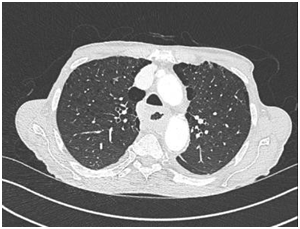

Fig 1 – Computed Tomography scan of the chest, abdomen and pelvis: severe relatively concentrical thickening of most of the oesophagus, especially of the oesophageal wall over approx- imately 15.5 cm in length